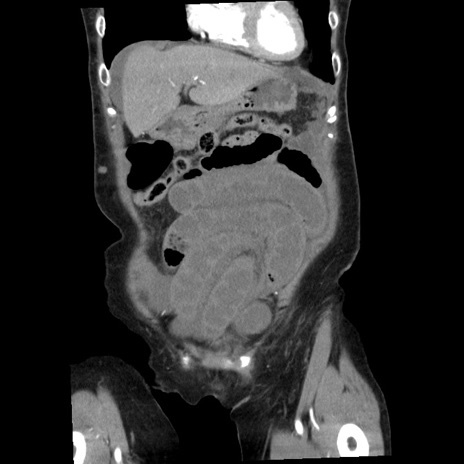

症例1(冠状断像)

【症例】80歳代女性

【主訴】腹痛

【現病歴】8時間前から腹痛あり来院。

【既往歴】糖尿病、脂質異常症、子宮体癌にて子宮全摘術

【身体所見】意識清明・会話良好だが腹痛で苦悶様、全腹部にわたって反跳痛と圧痛あり

【データ】WBC 13600、CRP 0.14、LDH 224、CK 90

横断像